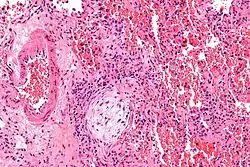

![]() | |

Micrograph showing a Masson body (off center left/bottom of the image – pale circular and paucicellular), as may be seen in cryptogenic organizing pneumonia. The Masson body plugs the airway. The artery associated with the obliterated airway is also seen (far left of the image). H&E stain. | |

Biopsy findings in patients with organizing pneumonia consist of loose connective tissue plugs involving the alveoli, alveolar ducts and bronchioles. The loose connective tissue plugs occupying the alveolar spaces often connect to other connective tissue plugs in nearby alveoli via the pores of Kohn creating a characteristic butterfly pattern on histology.[9] There is usually minimal to no interstitial inflammatory changes in biopsies of organizing pneumonia.[9]

Histologically, cryptogenic organizing pneumonia is characterized by the presence of polypoid plugs of loose organizing connective tissue (Masson bodies) within alveolar ducts, alveoli, and bronchioles.